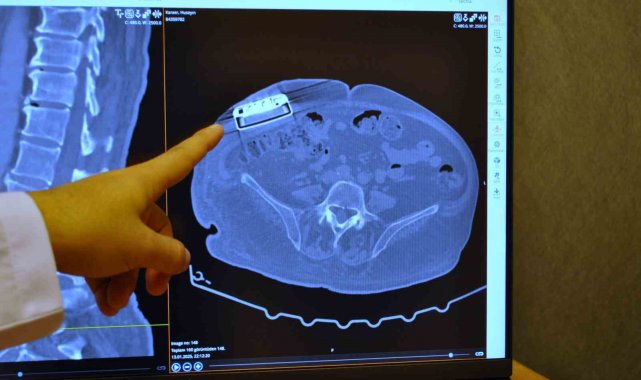

Baklofen pompasının, serabral palsi, mutipl skleroz (MS), omurilik yaralanmaları ve felç gibi durumlarda ortaya çıkan kas spazmı ve sertlik olarak kendini belli eden spastisiteyi tedavi etmek için kullanıldığını belirten Dr. Beşir Sürme, "Bu hastalarda ağızdan kullanılan ilaçlara bağlı yan etkilerinin olumsuz sonuçlarıyla karşılaşılmaması için pompa kullanılmaktadır. Cilt altına pompa ve omurilik kanalına da katateri yerleştirilir. Böylece kas spazmını engelleyecek ya da hafifletecek olan baklofen ilacı, pompa yardımıyla vücuda verilir. Pompa teknoloji sayesinde ilaç, hastayı yormadan verilmiş olur. Bu yöntem, hastanın tedavisinden sağladığı yararları artırmak ve daha güvenilir kılmak üzere hızla gelişiyor" dedi.

Operasyonla ilgili açıklamalarda bulunan Beyin ve Sinir Cerrahı Dr. Beşir Sürme, "65 yaşında erkek hasta, trafik kazasına bağlı bir omurilik hasarı geçiriyor ve bunun akabinde parapleji dediğimiz güç kaybı meydana geliyor. Gelişen bu omurilik hasarına bağlı hastada spastisite dediğimiz şiddetli kasılmalar oluşuyor ve hastaya baklofen pompası denilen bir cihaz implante ediliyor. Yaklaşık 11 sene önce implante edilen bu pompanın miadının dolması üzerine bize başvurdu ve biz bu hastamızda bir pompa değişimi ameliyatı gerçekleştirdik. Baklofen pompası tedavisi Türkiye'de daha önce de yapılan bir tedavi ancak biz yeni versiyon bir pompa yerleştirdik ve yeni özellikleri nedeniyle hastaya sağladığı özellikleri de gözlemledik" dedi.

Pompa tedavisinin daha önce uygulandığını ancak yeni teknoloji pompayı ilk kez erkek hastada kullandıklarını söyleyen Dr. Sürme, "Hastamızı yaklaşık 2 ay önce ameliyat ettik. Ameliyat sonrası programlamalarını yaptık. Bu hastalarda, hastalığın durumu ve hastanın ihtiyaçlarına göre verilecek ilacı pompa sayesinde programlayabiliyoruz. Programlamalardan sonra hastamız daha iyi olduğunu ve kasılmalarında belirgin düzelmeler olduğunu söylüyor. Hatta daha önceki pompaya göre şu an daha düşük doz ilaç vermemize rağmen hasta yine bundan fayda görebiliyor" şeklinde konuştu.